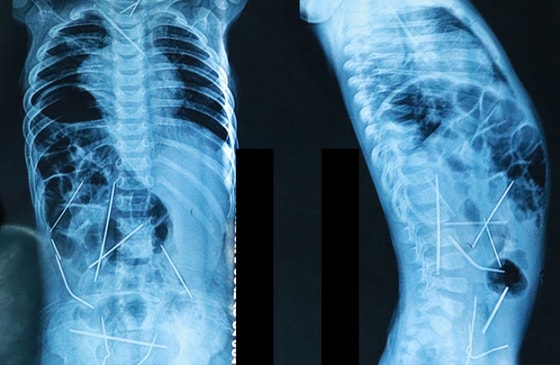

В теле 11-месячного младенца обнаружили 16 иголок, 13 из которых были извлечены.

В настоящее время состояние 11-месячного Азизбека Абдумажидова из Ферганы, в теле которого обнаружили 16 иголок, нормализовалось, сообщил Хабибулла Акилов, главврач Республиканского детского хирургического центра.

В теле ребенка осталось три иглы, однако их расположение не представляет угрозы для здоровья ребенка. По словам врача, после того, как мальчику исполнится 5-6 лет, их можно будет удалить. Об этом сообщает Darakchi.uz.